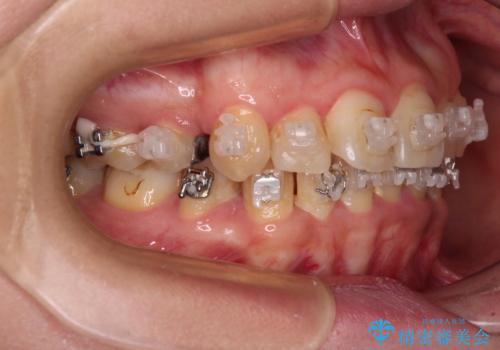

- 海外で抜歯矯正を開始し、治療途中で帰国したため、転院先を探しているとのことで来院された患者様です。

ワイヤーは抜けてしまい、後戻りが始まっている状態でしたが、既存の装置を継続利用して受け入れてくれる医院が見つからないとのことでした。

当院では、張り替える必要のある部位は張り替えることで継続することとし、抜歯スペースを閉じていくように治療を行うこととしました。